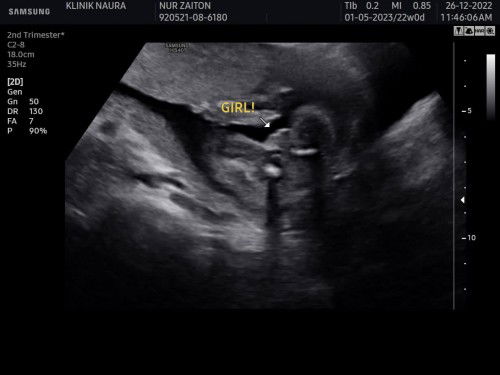

baby girl…

girl….dua org girl… no 3 doktor cakap girl jgk… xpa lah anak jnji sihat

my little princess